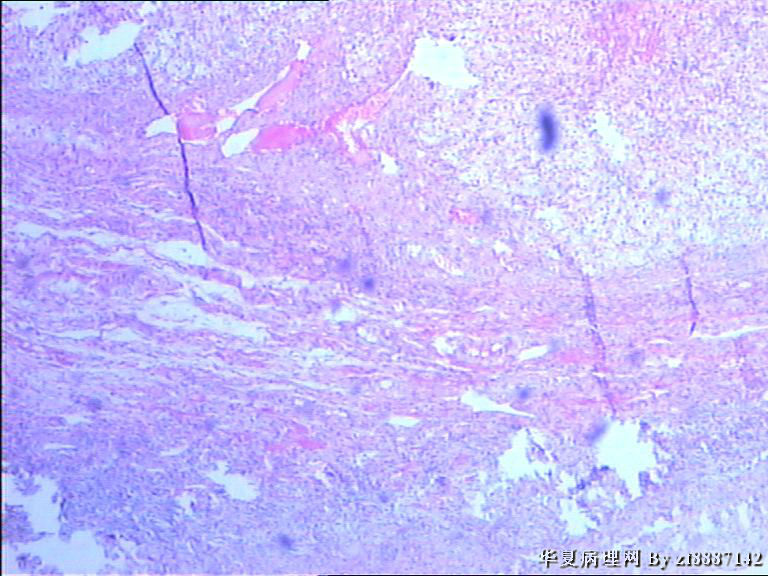

卵巢囊性肿块约3cm*3cm*3cm,表面光滑,包膜完整,内有清量液体,壁厚约0.3,